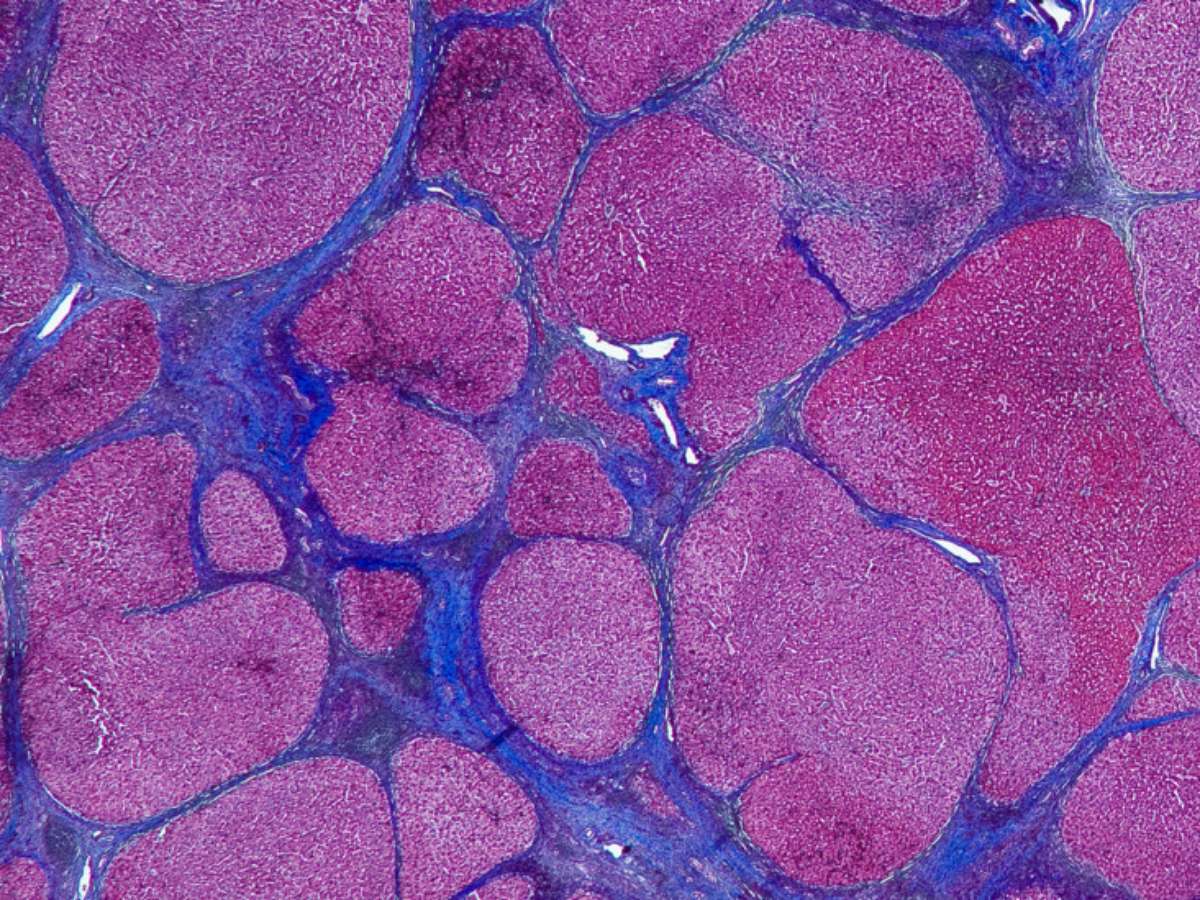

Livro de fotos publicado nos Estados Unidos mostra imagens inscríveis a partir de doenças devastadores. Entre elas está a de um fígado, um dos maiores órgãos do corpo humano, com cirrose, que ocorre quando o tecido do órgão (em vermelho) é substituído por tecido fibroso (azul). Na tentativa de se regenerar, as células do fígado se proliferam, mas ficam contidas pelo tecido fibroso, resultando na formação de nódulos

Foto: Hidden Beauty: Exploring the Aesthetics of Medical Science / BBC News Brasil